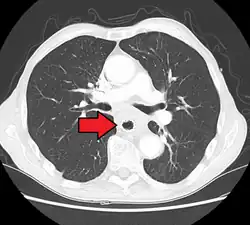

Additional testing is needed to assess how much the cancer has spread (see § Staging, below). Computed tomography (CT) of the chest, abdomen and pelvis can evaluate whether the cancer has spread to adjacent tissues or distant organs (especially liver and lymph nodes). The sensitivity of a CT scan is limited by its ability to detect masses (e.g. enlarged lymph nodes or involved organs) generally larger than 1 cm.[44][45] Positron emission tomography is also used to estimate the extent of the disease and is regarded as more precise than CT alone.[46] PET/MR as a novel modality has shown promising results in preoperative staging with fair feasibility and good correlation in comparison to PET/CT. It can enhance tissue differentiation with lowering the radiation dose to the patient.[47] Esophageal endoscopic ultrasound can provide staging information regarding the level of tumor invasion, and possible spread to regional lymph nodes.

Contrast CT scan showing an esophageal tumor (axial view)

Contrast CT scan showing an esophageal tumor (coronal view)